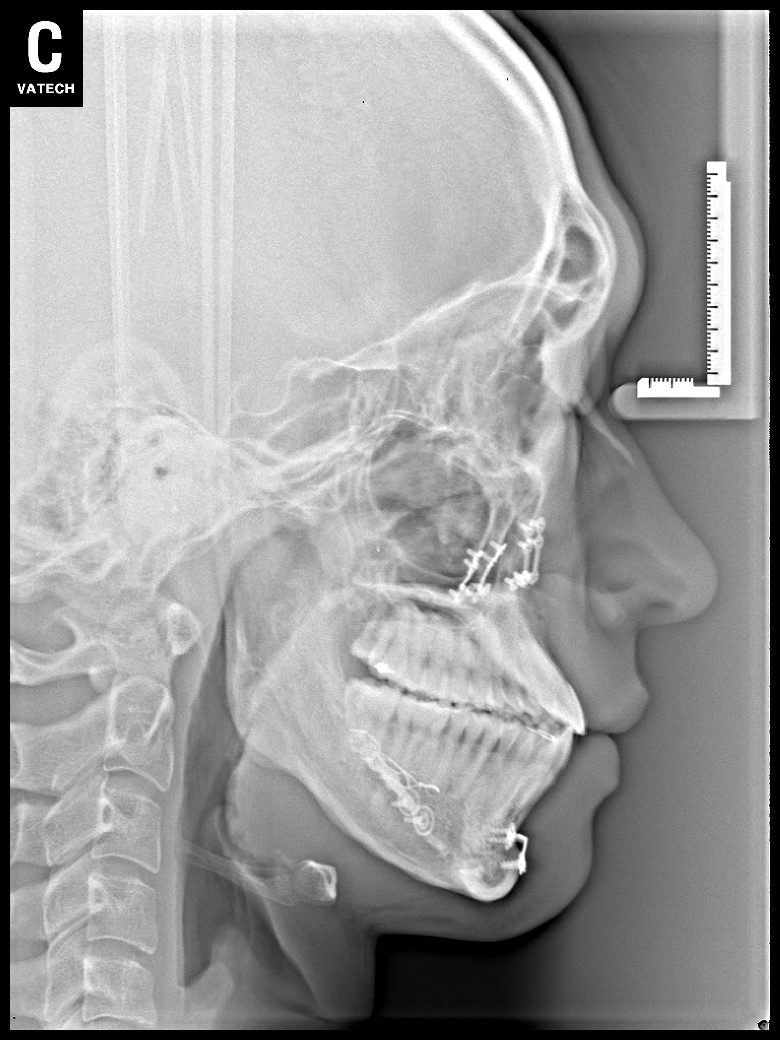

치료 후 사진입니다.